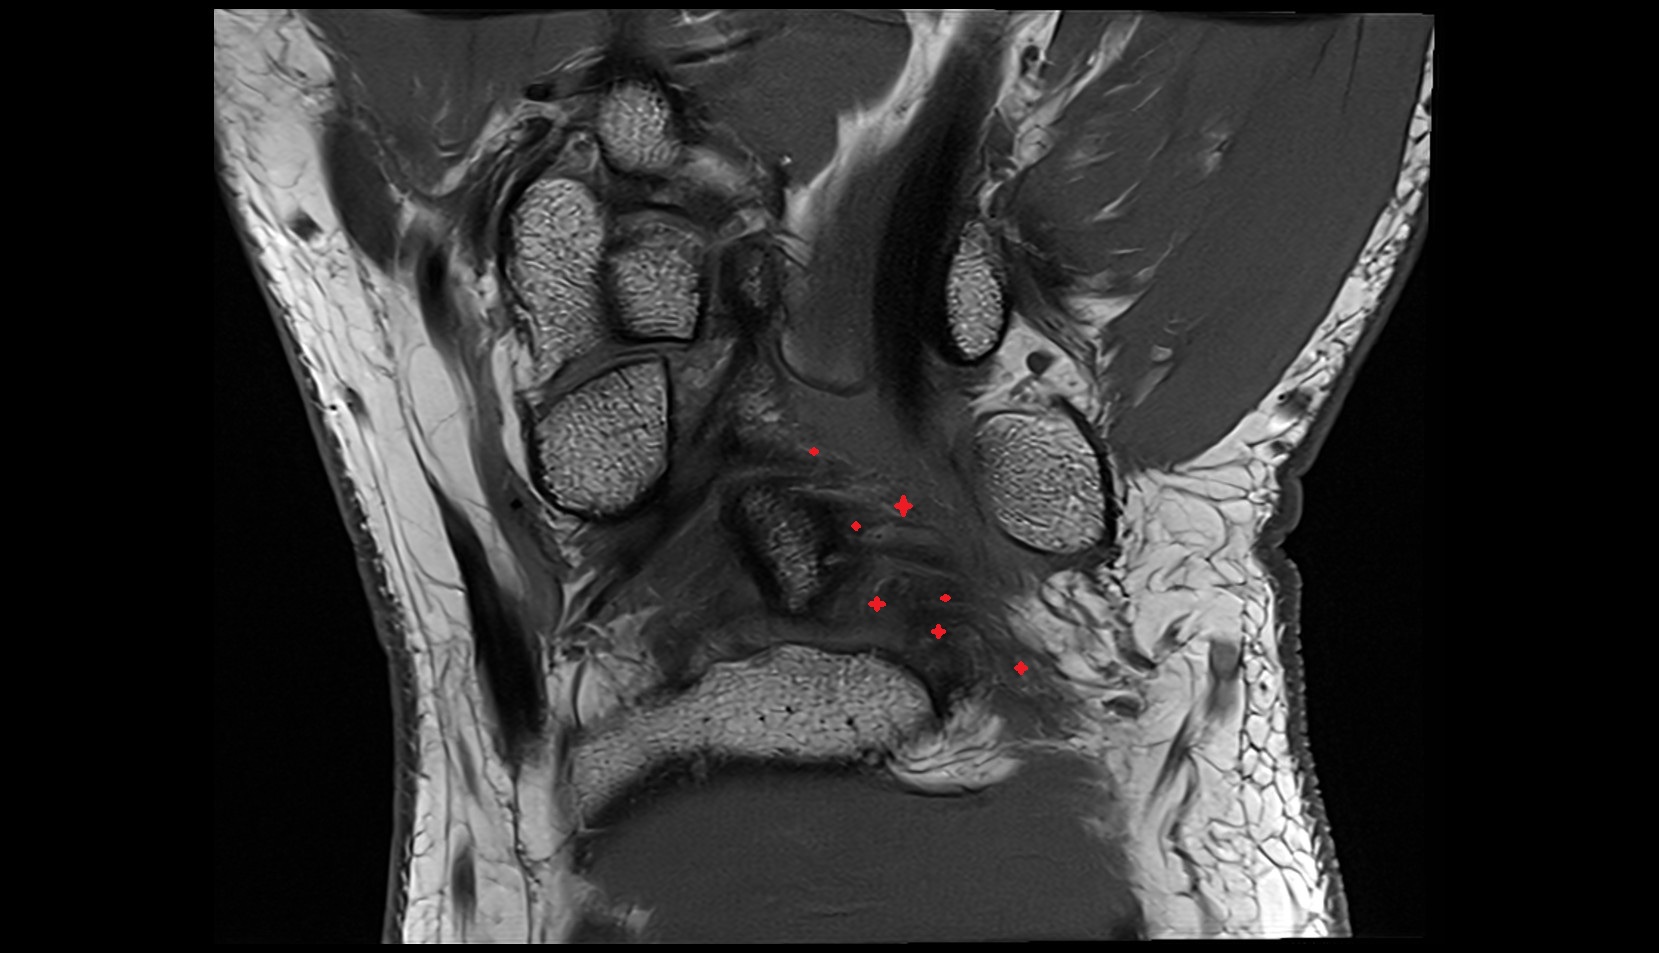

- Medial meniscus

- Lateral meniscus

- Anterior horn of lateral meniscus

- Posterior horn of lateral meniscus

- Body of lateral meniscus

- Anterior root of lateral meniscus

- Posterior root of lateral meniscus